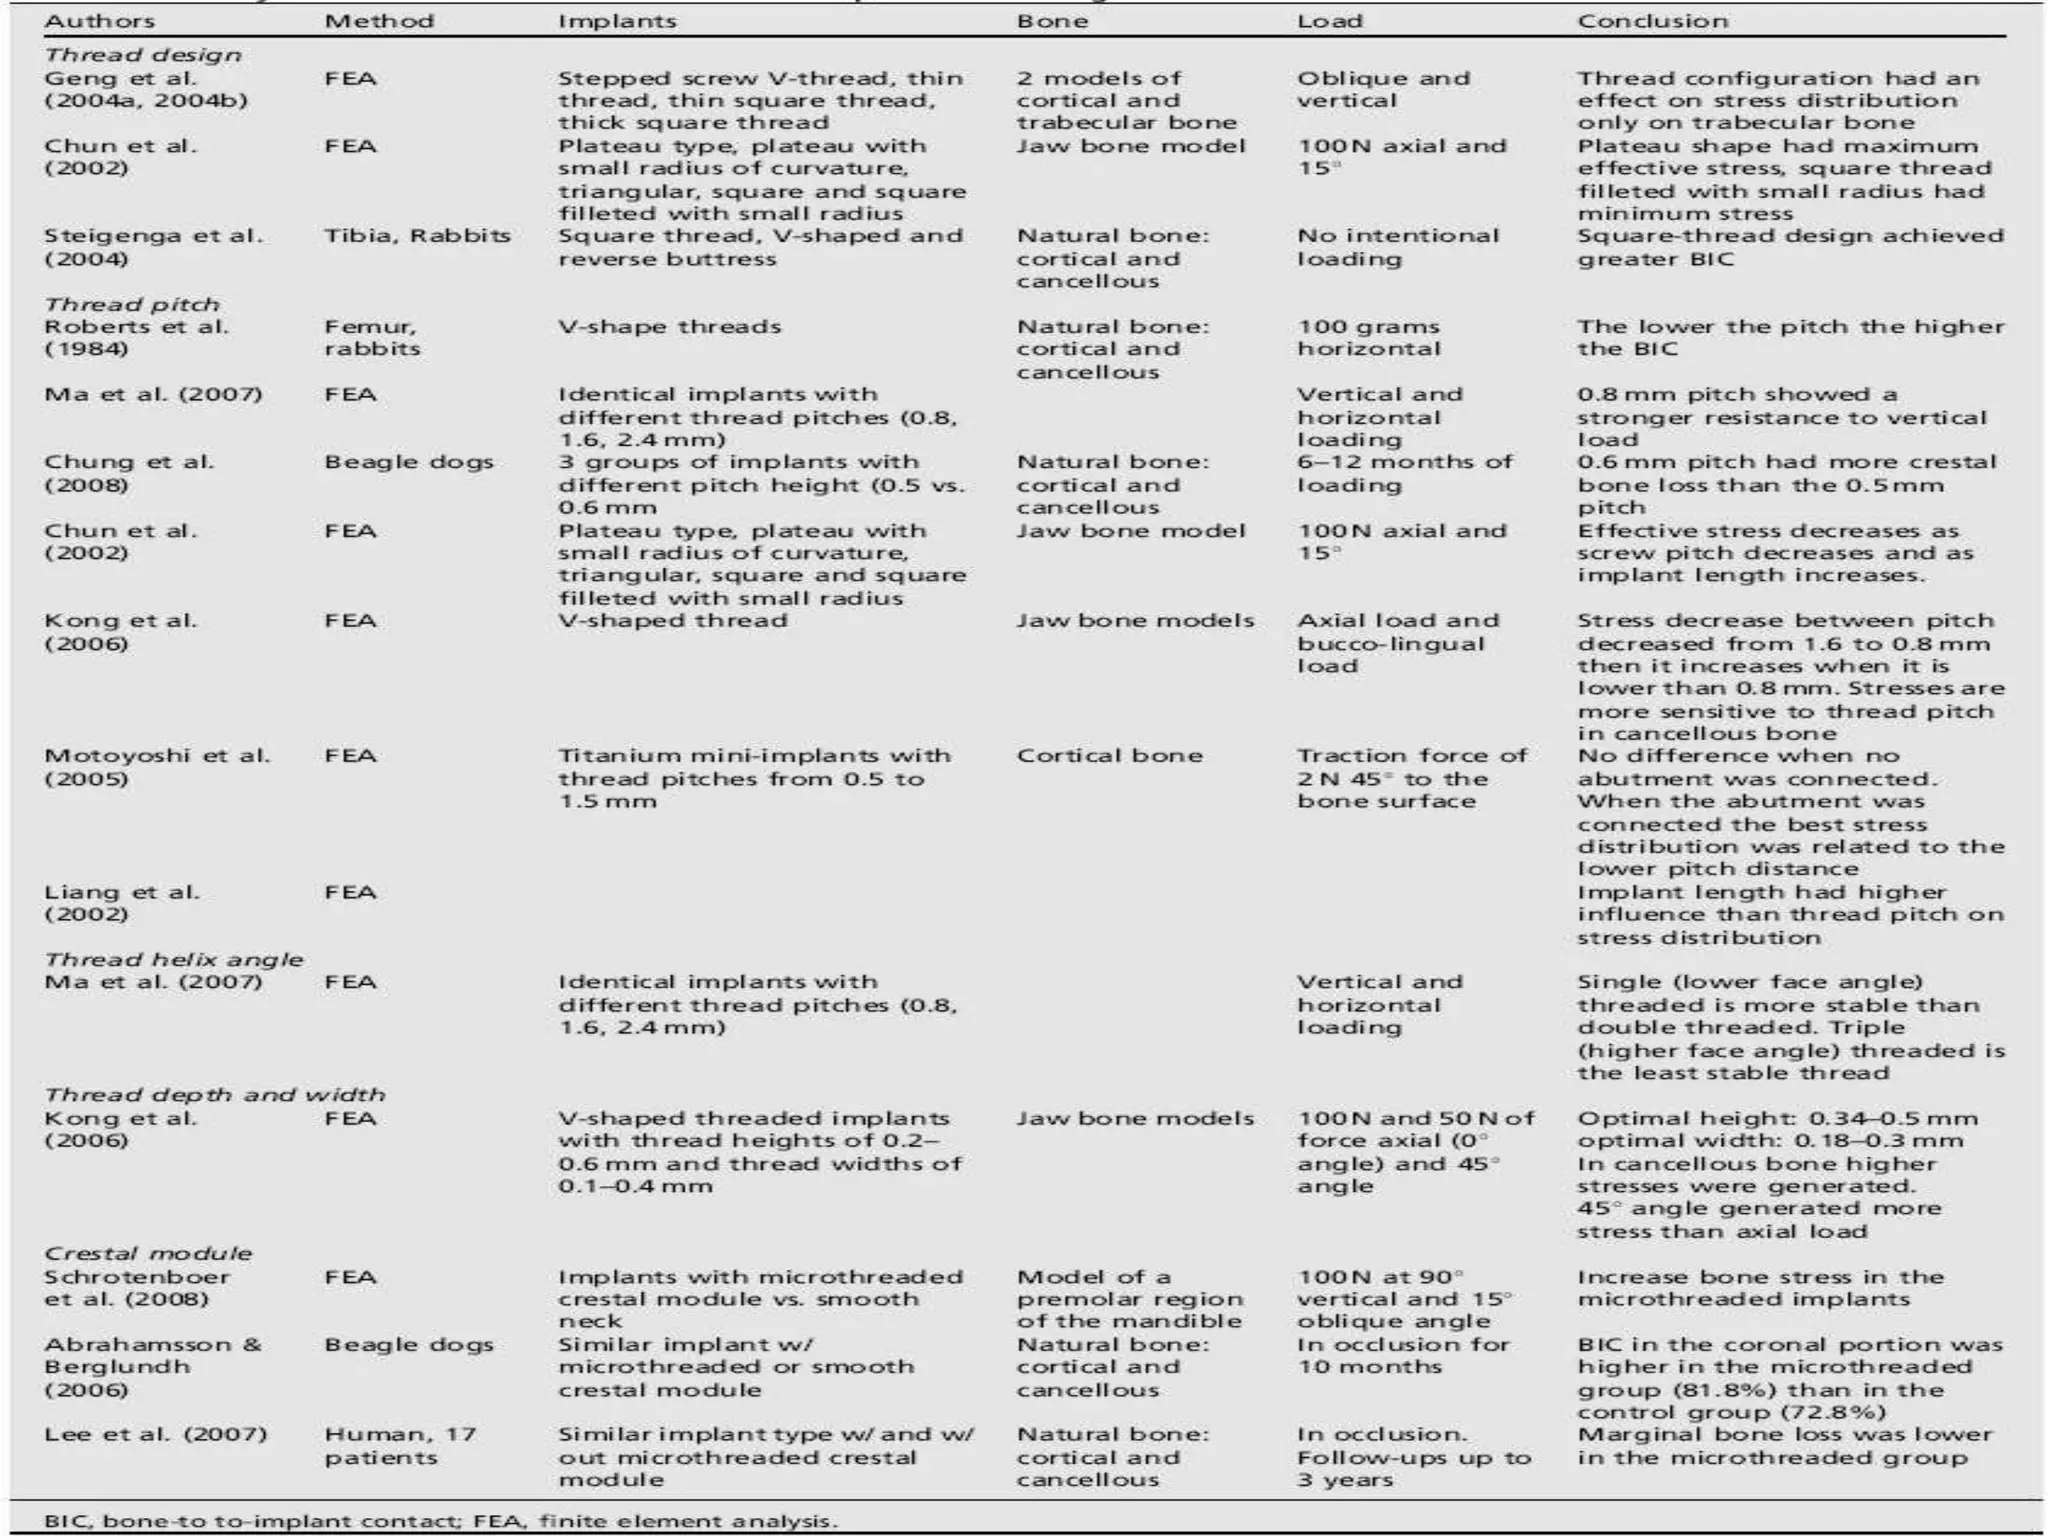

This document discusses factors that influence osseointegration and primary stability of dental implants, including implant design characteristics, surgical technique, and loading protocols. Specifically, it covers the processes of osseointegration and how forces on implants can either promote or inhibit bone remodeling. Key implant design considerations like length, diameter, threads, coatings and surface topography are analyzed in terms of their effects on stress distribution and bone-implant contact. The importance of primary stability and factors influencing it like bone quality and surgical skill are also addressed. Loading protocols ranging from immediate to conventional loading are compared.